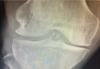

Achado clássico em RX

Erosão em saca-bocados